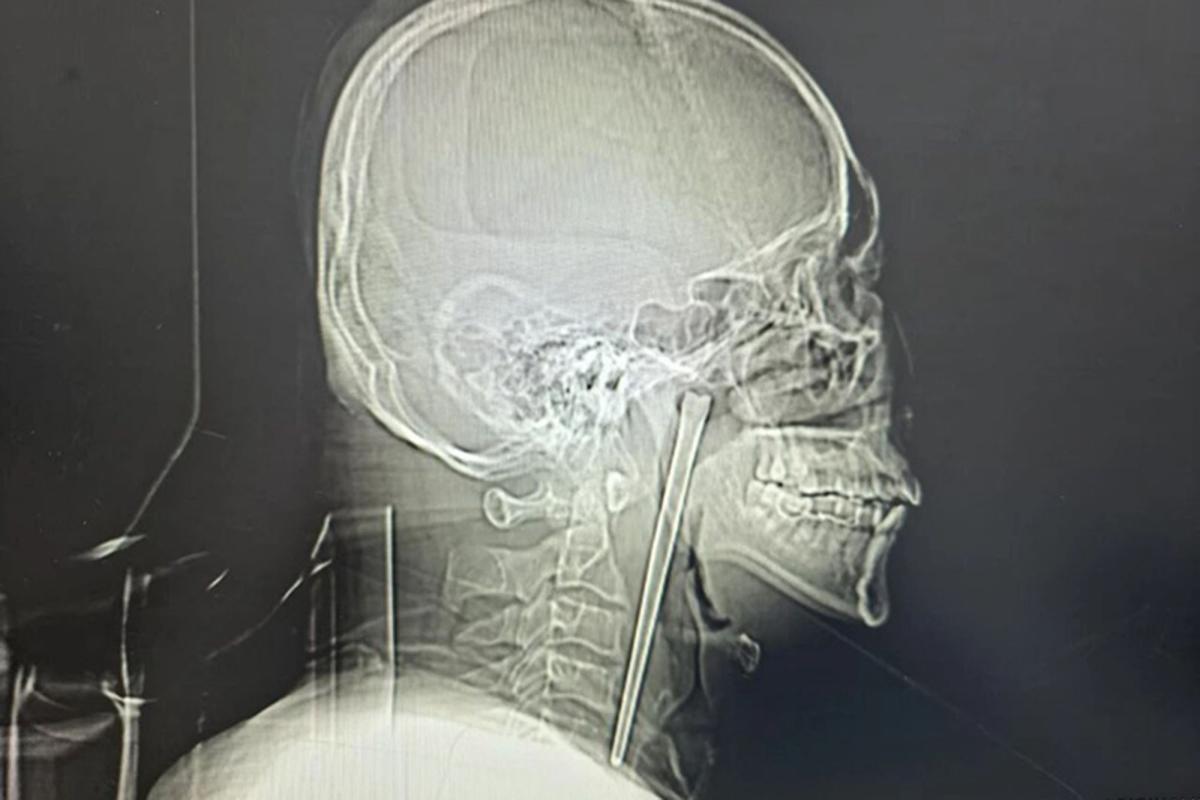

During the chaos, 20-year-old forward Dominic Frimpong, who was on loan from Aduana FC, sustained a gunshot wound to the head.